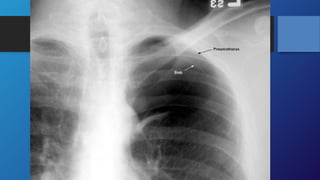

Investigations

•Chest X-RAY is the diagnostic test in most cases.

1. Revealing a visible lung edge and absent lung markings peripherally.

2. Blunting of the ipsilateral costophrenic angle due to low-volume

bleeding into the pleural space.

3. Pneumothoraces are difficult to visualize on supine films.

4. Look for a sharply delineated heart border.

5. Hemidiaphragm and costophrenic angle depression (‘deep sulcus

sign’),

6. Increased lucency on the affected side

Investigations •Chest X-RAY isthe diagnostic test in most cases. 1. Revealing a visible lung edge and absent lung markings peripherally. 2. Blunting of the ipsilateral costophrenic angle due to low-volume bleeding into the pleural space. 3. Pneumothoraces are difficult to visualize on supine films. 4. Look for a sharply delineated heart border. 5. Hemidiaphragm and costophrenic angle depression (‘deep sulcus sign’), 6. Increased lucency on the affected side

Investigations Chest X-RAY isthe diagnostic test in most cases.